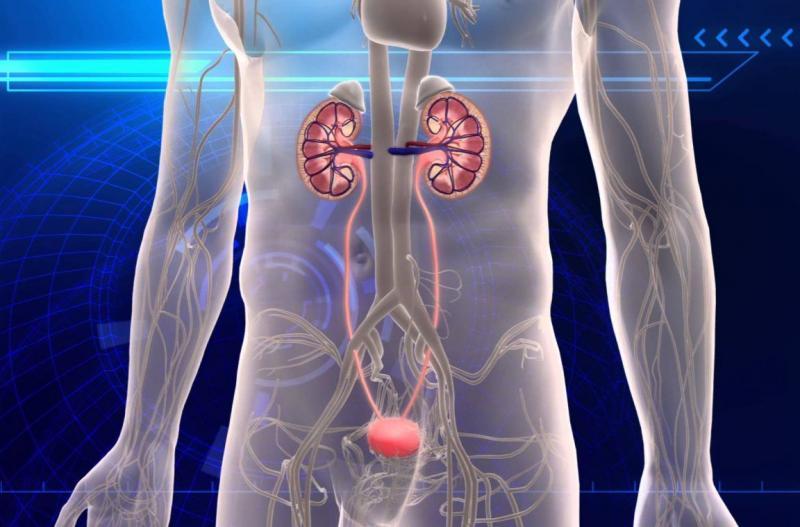

Urinary tract obstruction treatment devices are used to remove urinary obstructions that hinder the normal flow of urine from the kidneys to the bladder. These devices treat various conditions such as kidney stones, bladder stones, enlarged prostate, and urinary tract infections. Minimally invasive surgeries using these devices offer benefits like reduced procedural time, minimal incisions,...